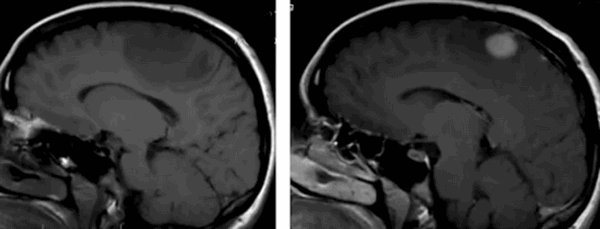

Нативная и контрастная МРТ: после усиления видны множественные мелкие метастазы головного мозга

Распознать опухоль головного мозга с помощью МРТ без контраста можно на продвинутой стадии. Малые новообразования скульптурируются значительно хуже или не видны совсем, что снижает ценность исследования. При высокой напряженности поля можно сделать нативную МРТ, снимки будут хорошего качества. Магнитно-резонансная томография выдает изображения в зависимости от запрограммированного типа сканирования, контрастирование упрощает выявление опухолей на любой стадии развития, проведение дифференциального диагноза между доброкачественным и злокачественным процессом. Побочные эффекты на введение препарата на основе хелатов гадолиния развиваются крайне редко, меньше чем у 1% людей. При наличии показаний отказываться от контрастного усиления не стоит. Пациентам, страдающим почечной или печеночной недостаточностью в декомпенсированной стадии, может быть выполнена обычная МРТ. Магнитно-резонансное сканирование без динамического контрастирования на томографе с небольшой мощностью обнаружит объемное поражение головного мозга значительных размеров. После внутривенного введения парамагнетика можно более точно определить локализацию, объем, степень инвазии, рассмотреть кровоснабжение опухоли, оценить индивидуальные особенности, что имеет значение для планирования лечения.